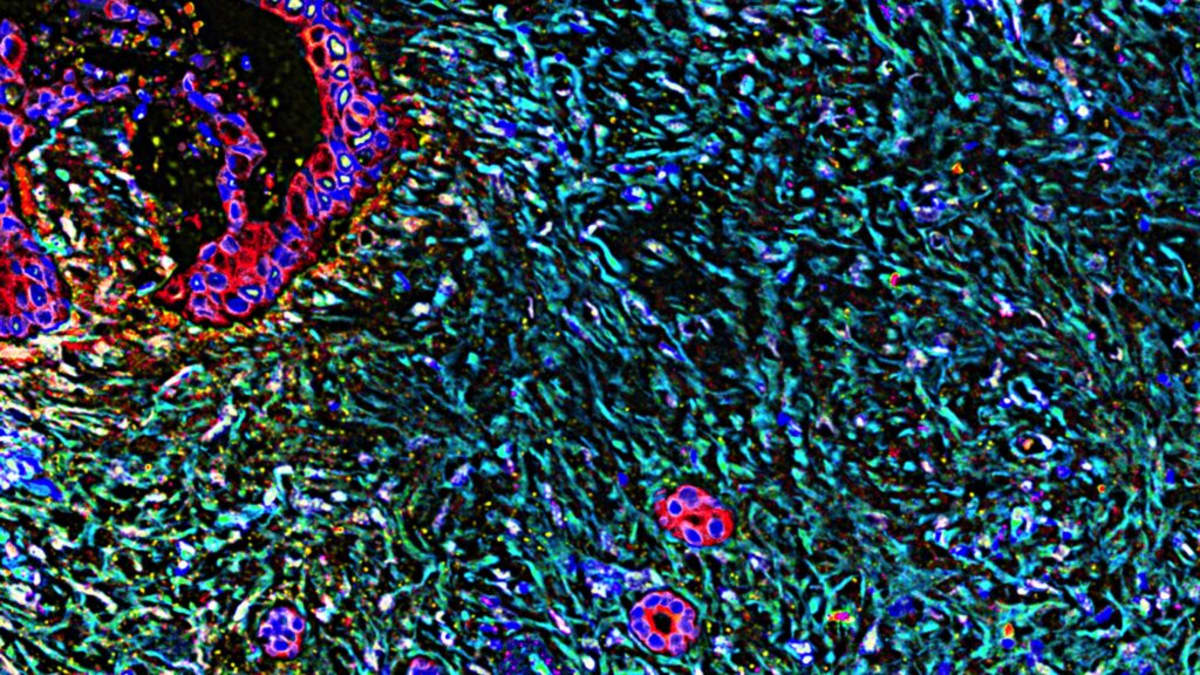

A new pill for pancreatic cancer helped patients live nearly twice as long as standard chemotherapy in a groundbreaking study.

The experimental drug could bring hope to one of the deadliest cancers within months.